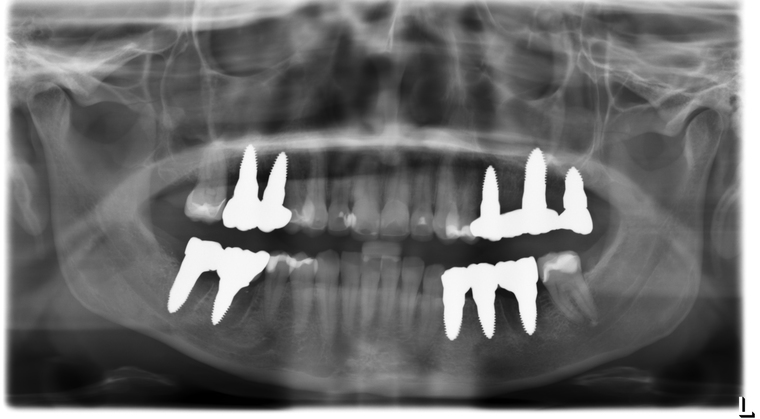

Ein Tätigkeitsschwerpunkt unserer Praxis in Salzburg ist die Implantologie. Wenn ein Zahn fehlt oder entfernt werden muss, sollte immer die Möglichkeit der Implantation im Vordergrund stehen. Ein Implantat verhält sich von den Eigenschaften genau so wie ein natürlicher Zahn. Egal ob nur ein einzelner Zahn vom Zahnarzt ersetzt werden muss oder ein ganzer Kiefer mit festsitzendem Zahnersatz versorgt werden soll, wir finden für Sie eine Möglichkeit, auch wenn die Voraussetzungen ausweglos erscheinen. Wenn möglich versorgen wir unsere Patienten mit Keramikimplantaten. Diese sind immun-neutral und können sehr oft direkt bei der Zahnextraktion eingesetzt werden. Für unsere Patienten ist daher meist nur ein operativer Eingriff notwendig!

- 3D-Röntgentechnik, 3D-Implantatplanung und virtuelle Implantation